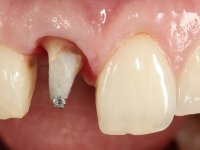

The treatment began with the placement of an intraradicular post and the creation of a new composite resin restoration. This procedure was performed with a surgical approach that allowed the remaining margins to be completely exposed, which were shown to be at a very infra-gingival level. Simultaneously, the periodontal pocket was curetted and root scaling and root planning of adjacent teeth were performed. Two months after this first intervention, the making of the crown began. A pre-print on silicone was performed to make a temporary crown with dual-cured composite resin. Gingival retraction was performed using the technique of kaolin paste compressed by the provisional crown. The impression was made using the double-mix technique with double viscosity with quick-setting silicone. In the laboratory, a crown with a ceramic-coated Zr infrastructure was made. The crown slightly overlapped tooth 12, allowing a dimensionally mimicry of the symmetrical tooth. Its fit was confirmed and approved by the patient; it was definitively cemented with resin-reinforced glass ionomer cement.